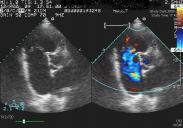

三尖瓣關閉不全

• 三尖瓣關閉不全

628健康網為您分享有關三尖瓣關閉不全的癥狀,三尖瓣關閉不全的治療方法,三尖瓣關閉不全的預防知識,三尖瓣關閉不全的癥狀...